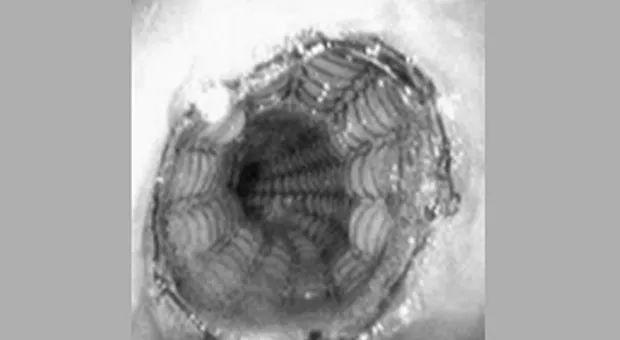

4. Esophacoil (Medtronic/Instent, Eden Prairie, Minnesota) представляет собой стент в виде пружины состоящей из одиночной плоской никель-титановой проволоки плотно скрученной в спираль и с выступающими краями. Система доставки имеет размеры 30F и дает выбор начала открытия с центра, а также с дистального или проксимального конца. Хотя этот стент обладает наибольшей силой радиального расширения, он имеет и наибольший уровень ретракции (укорочения) после установки [6].

Иллюстрация №3: Стент Esophacoil